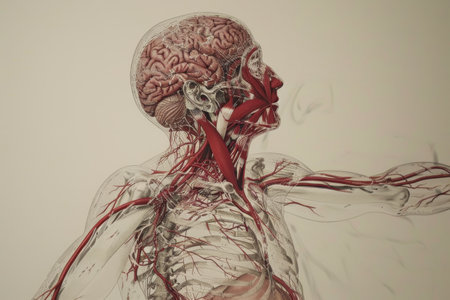

Vibrant illustration of human anatomy showcasing the brain and neck. Ideal for medical, educational, and health-related projects to highlight inner workings.

This artistic visualization depicts the human anatomy, highlighting the brain, spine, and nervous system in vibrant red hues. Aimed at educational and medical audiences, this model enhances comprehension of human physiology.